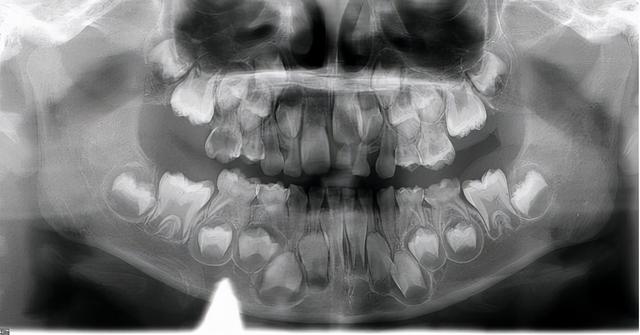

病房里,刚刚醒来的肖鑫(化名)正和妈妈一起照镜子看自己的新牙。两个小时前,肖鑫还满是蛀牙。经过舒适治疗,这些问题都得到了妥善解决。

小新6岁了。他喜欢吃零食,但不喜欢刷牙。慢慢地,口腔里出现了蛀牙。一开始父母没注意,以为反正要换牙,就放了。结果孩子嘴里的蛀牙越来越多,甚至疼痛影响进食。

对肖鑫来说,他只是静静地“睡”着。当他醒来时,他的蛀牙变成了新牙,其中几颗牙齿穿着闪亮的“盔甲”。整体口腔环境焕然一新,他不再害怕吃东西和伤害牙齿。

龋齿是儿童最常见的口腔疾病之一。我国儿童患龋率较高。据统计,3岁儿童患龋率为50%,5岁儿童患龋率高达近71%。

吴志芳主任:很多家长认为乳牙蛀牙不需要治疗。这种误解不及时治疗是不可能存在的。随着口腔微生物环境的变化,会导致龋齿越来越多,龋齿对儿童健康的危害也很大。比如龋齿引起的疼痛会影响进食,导致孩子养成单侧咀嚼的习惯,大大小小的脸,大量的龋齿,甚至影响孩子的生长发育;如果炎症涉及恒牙胚,会影响恒牙的发育;前牙过早缺失会影响发音,伤害孩子的自信心。反复的根尖周炎症可导致间质感染、严重发热甚至心肌炎。

一般情况下,孩子从6岁开始换牙,一直到12岁,所有乳牙脱落,恒牙更换,男孩可能会推迟到第一年的第一天和第二天更换,间隔至少6年。吴志芳主任说:“蛀牙会进步,一味等待换牙。在此之前,小游的口腔状况可能很差,到时候治疗会很困难。比如烂根要拔出来当缺口托;牙齿脱落会影响后续牙齿的萌出;牙齿排列不整齐,还要面对正畸治疗等等。总而言之,越早就医,治疗越简单,费用越便宜。”